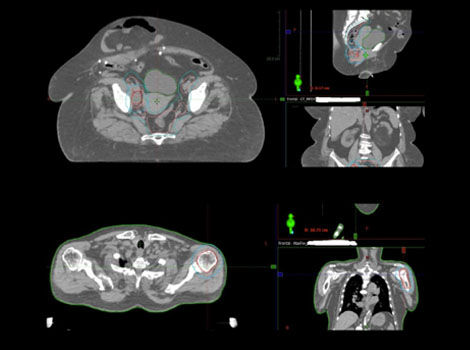

Deep Learning-based MaxFOV 2

Specify CT scan accuracy with a full 80 cm field of view.

The precise dose calculation in CT simulation requires the full and accurate view of the patient’s skin line and tissue densities. In practice, truncation often occurs in CT images due to the limited display field-of view(DFOV), extra-large patient size, or the unique off-centered patient positioning needed to accommodate immobilization devices.

MaxFOV 2 is an AI-powered, extended-Field-of-View technology that extends DFOV up to 80 cm, with specified accuracy

• ±2 mm skin line accuracy with ±40 HU accuracy of water for truncation up to 70 cm

• ±3 mm skin line accuracy with ±60 HU accuracy of water for truncation up to 80 cm*

MaxFOV 2 has the potential to increase your confidence in high accuracy of patient contour and tissue density determination sufficient for dose calculation.

* As demonstrated by phantom testing, accuracy value can be reproduced using GE recommended testing method